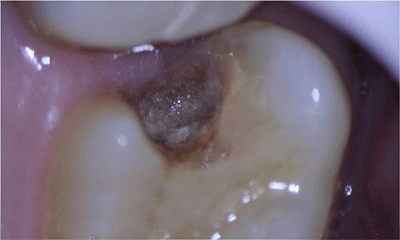

术前照

术前显微镜影像